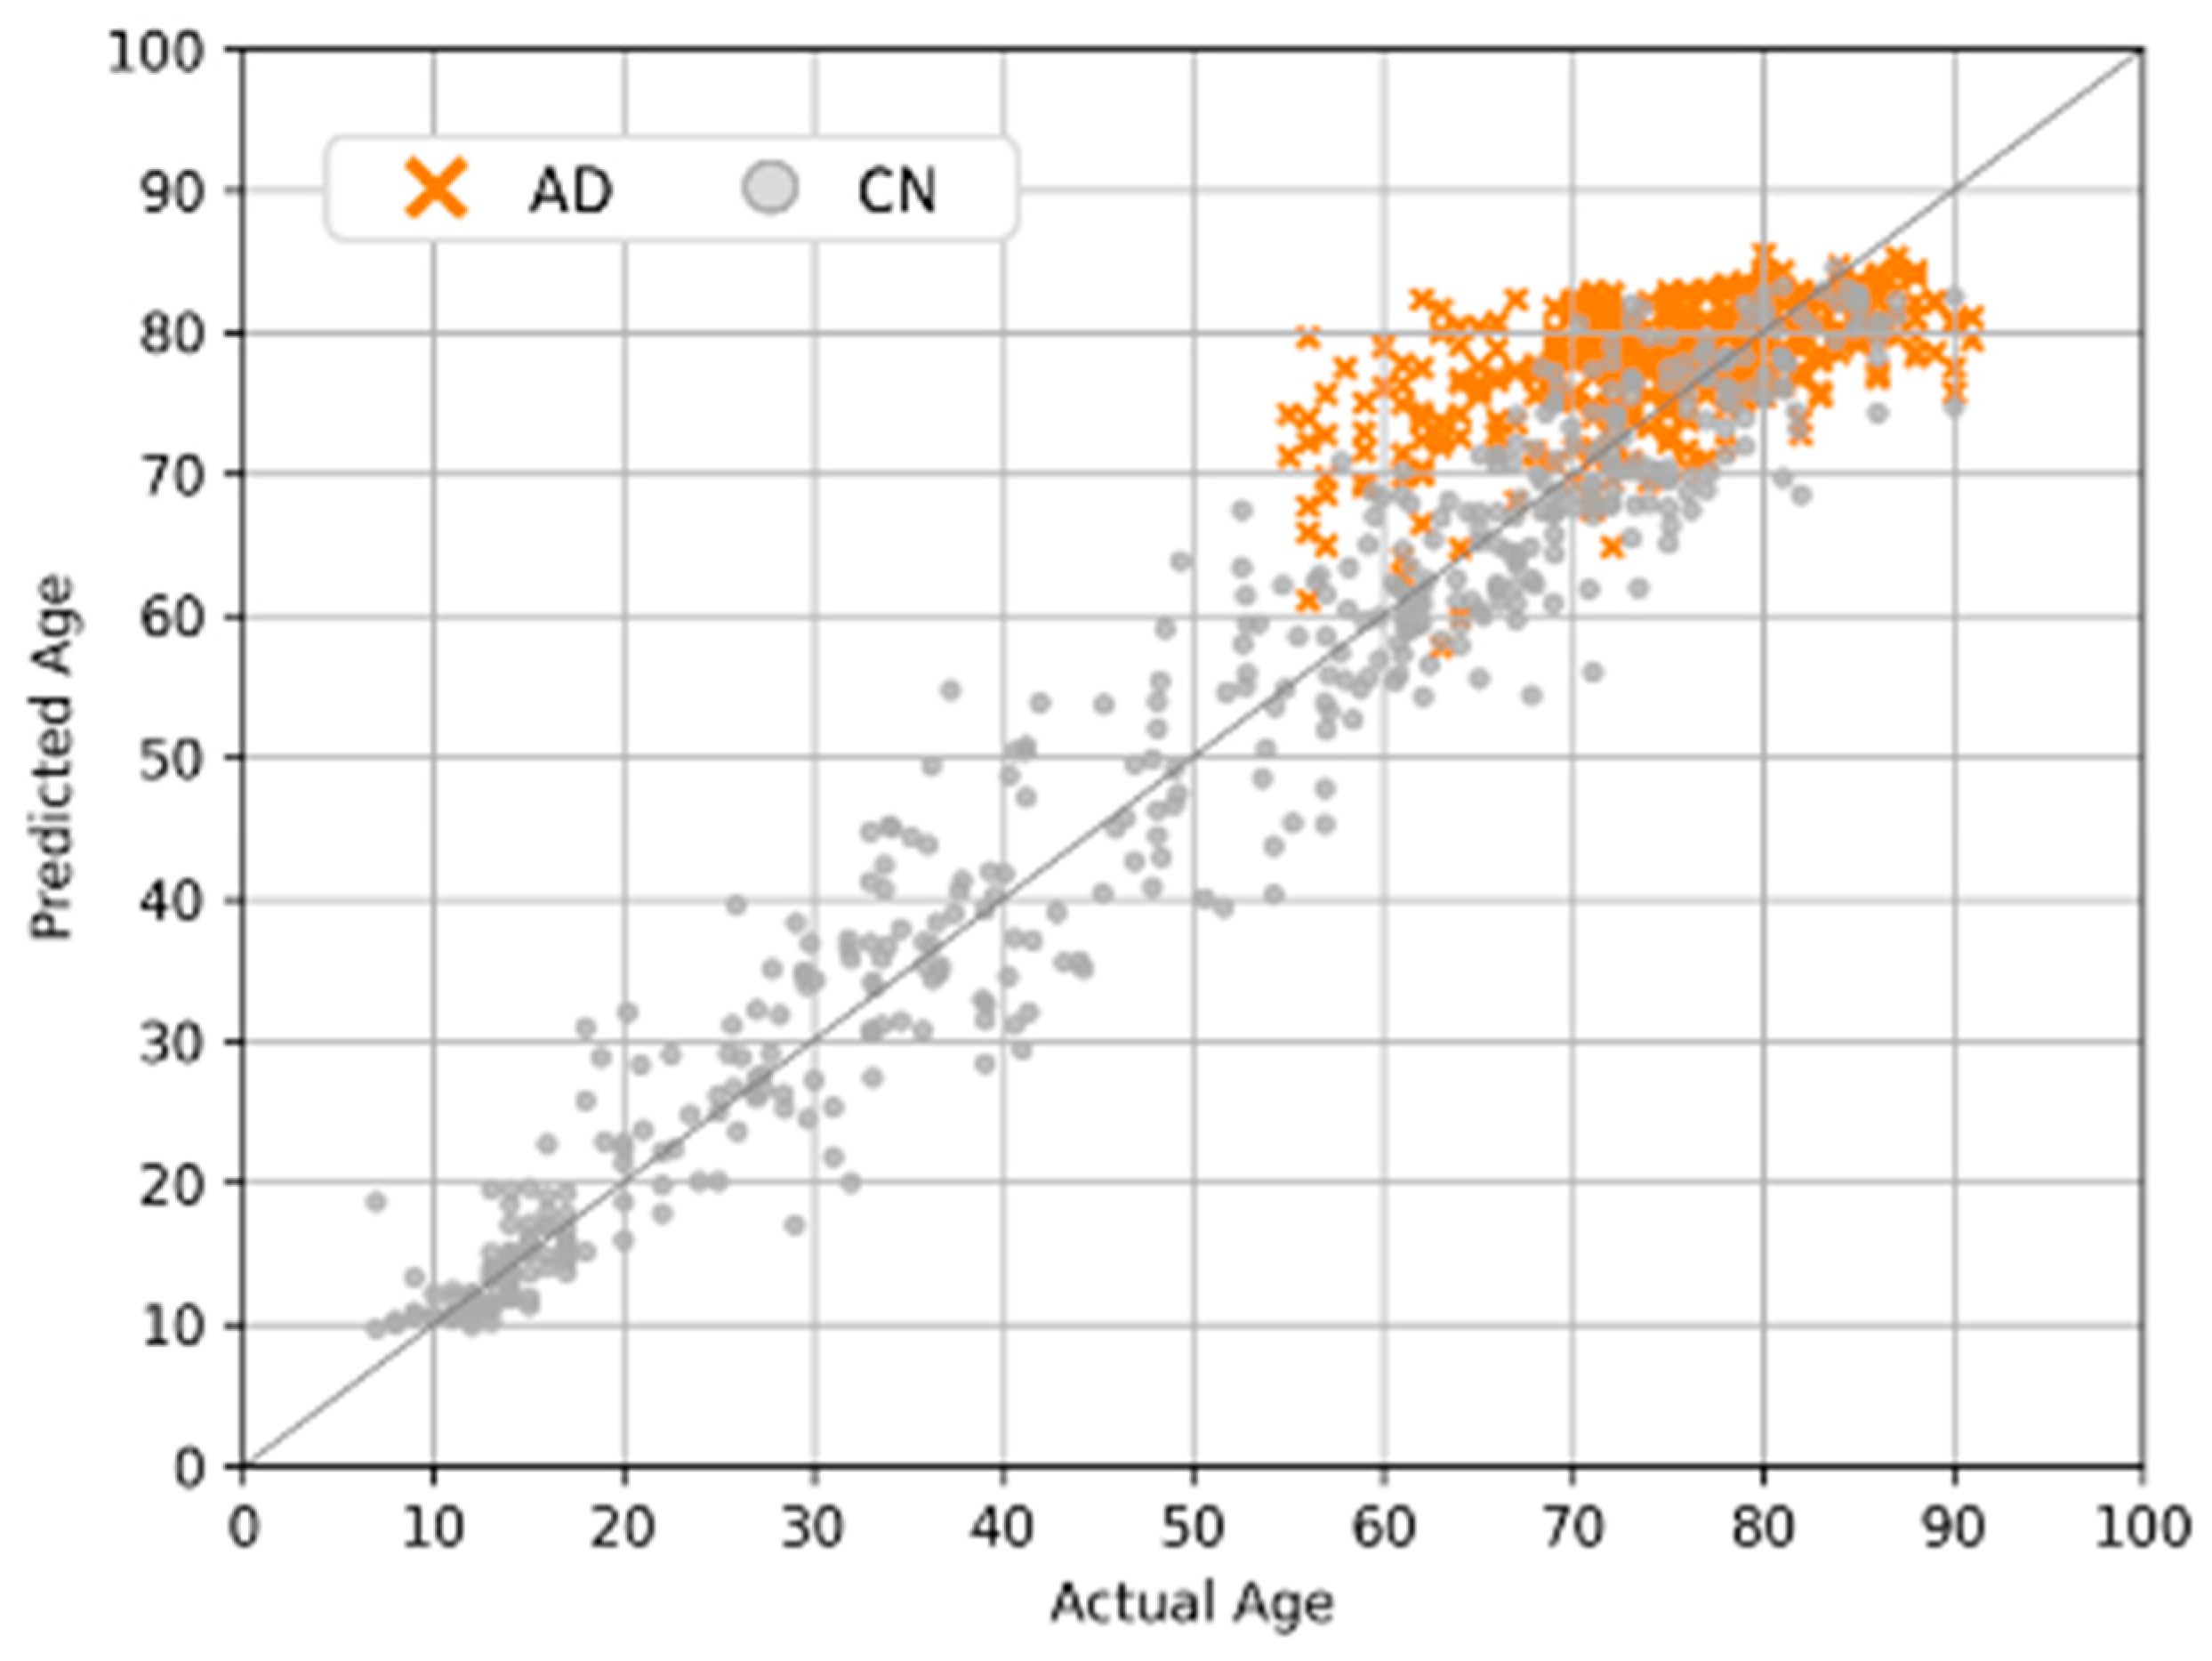

4.5. Clinical Applications and Efficacy Assessment